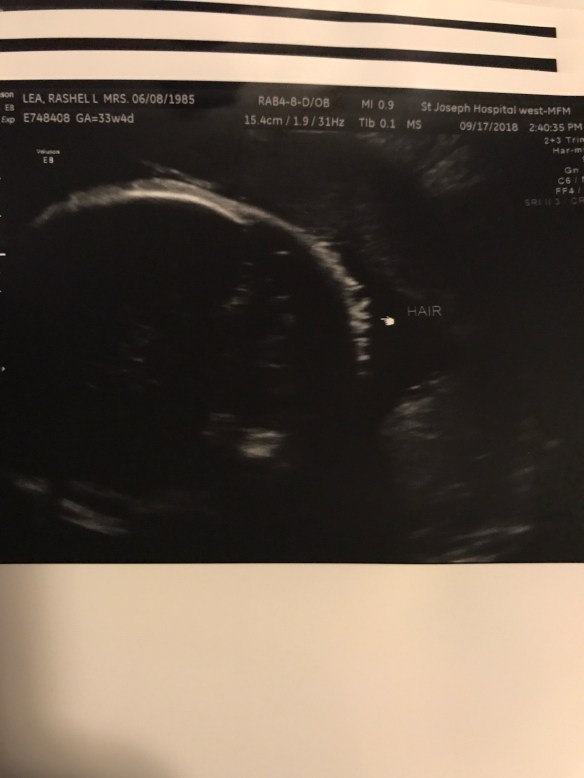

Well the last 4 weeks has been quite a whirlwind. During some of our ultrasounds baby B was measuring just a little behind in his legs. I didn’t think much of it but my dr decided to send us to a specialist just to make sure. She basically said worst case scenario would be dwarfism and best case would be he’s just short. Obviously that was not what anyone wanted to hear. We all want our babies to be as perfect as they can be. We had to schedule out the appointment for about a week or two after. Lucky they got us in pretty quickly! We were able to get great news this week that he looks just fine! Yes his legs are a little short but he seems just fine! What a relief this was for J and K! So we had our regular OB appointment today and he still looks good except for he won’t move to the head down position!!!! He likes to be transverse. He’s a stinker. So we will now be trying acupuncture! I’m also trying the warm on the bottom of my belly and the cold by his head to encourage him to move south! We still have time for him to get it together. Obviously I want to avoid a c section. I feel terrible and selfish sometimes saying that… obviously if it’s an emergency or nothing can be done then I just want him here safe and sound with his parents. I just know how hard it was physically and emotionally for me to heal after my one c section. It’s way more painful and takes a lot longer to get back to normal. So send me all the prayers and good vibes you guys have for a wonderful safe vaginal delivery! Exciting news J was able to feel baby B move around a bit! We tried to guess what part of his body it could possibly be! In all of his pictures he likes to keep his hands and feet right by his face! We’re actually impressed how he does it! He’s a little acrobat! So I have acupuncture next week then the next week A regular ob appointment. Then I go every week so at my 37 week we will have another growth scan at the specialist and then another ob appointment to check me! My dr will be out of the office for that appointment but will be back for the next one I believe! Oh we also did hospital tours while they were in town! That’s fun for them! I remember feeling excited to pick where I was having my baby. I wanted them to have the same experience that most get. Well I believe that’s all I have for right now. I’ll add some pictures for fun!